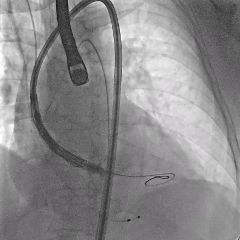

术中影像

脱钩后造影,瓣膜无位移,可见瓣周漏

20mm球囊后扩,瓣膜形态改善

后扩后评估,可见少量瓣周漏

最终瓣膜位置稳定